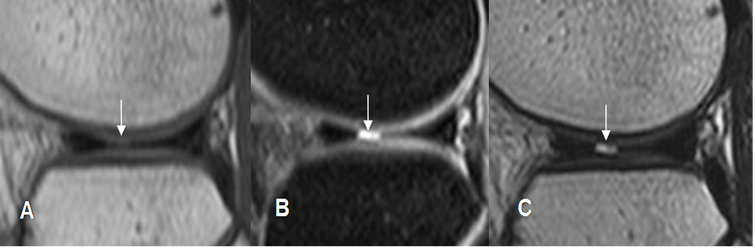

Fig 76. Ruptura meniscal radial.

A: RM sagital en T1, B: RM sagital en STIR y C: RM sagital en T2. Defecto en la parte medial del cuerno anterior del menisco, por ruptura radial.